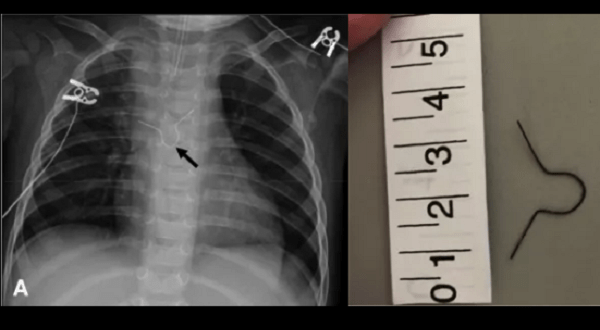

Además durante el escáner se descubrió un objeto metálico alojado dentro de su esófago, el cual resultó ser un gancho metálico decorativo, con el que generalmente se cierran las bolsas de plástico para pan.

El gancho se clavó en el esófago, provocando una infección que se propagó hacia el cerebro y llegó a causarle convulsiones a la pequeña, según un informe médico publicado en The Journal of Emergency Medicine.

Los médicos administraron antibióticos y realizaron una cirugía cerebral para drenar el líquido de algunos de los abscesos, así como el cuerpo ajeno.